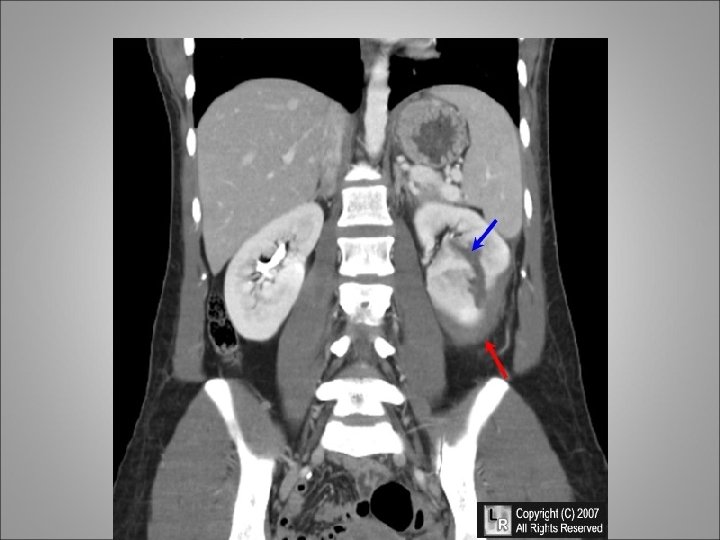

URETEROPELVIC JUNCTION DISRUPTION • Three classic findings on triphasic CT are associated with UPJ disruption: (1) good renal contrast agent excretion with medial extravasation of contrast agent in the perirenal and upper ureteral area; (2) absence of parenchymal lacerations; and (3) no visualization of the ipsilateral distal ureter • In the clinically stable patient in whom the diagnosis is made within 5 days after the traumatic insult it is preferred to proceed to immediate surgical repair with débridement of any devitalized tissue, spatulation and reanastomosis of the ureter over a stent • In patients with a delayed diagnosis of 6 or more days it is preferred to place a nephrostomy tube and allow the patient and injury to stabilize for 12 weeks • The combination of remaining renal function and the length of the surgical defect allow the surgeon to make the proper surgical planning